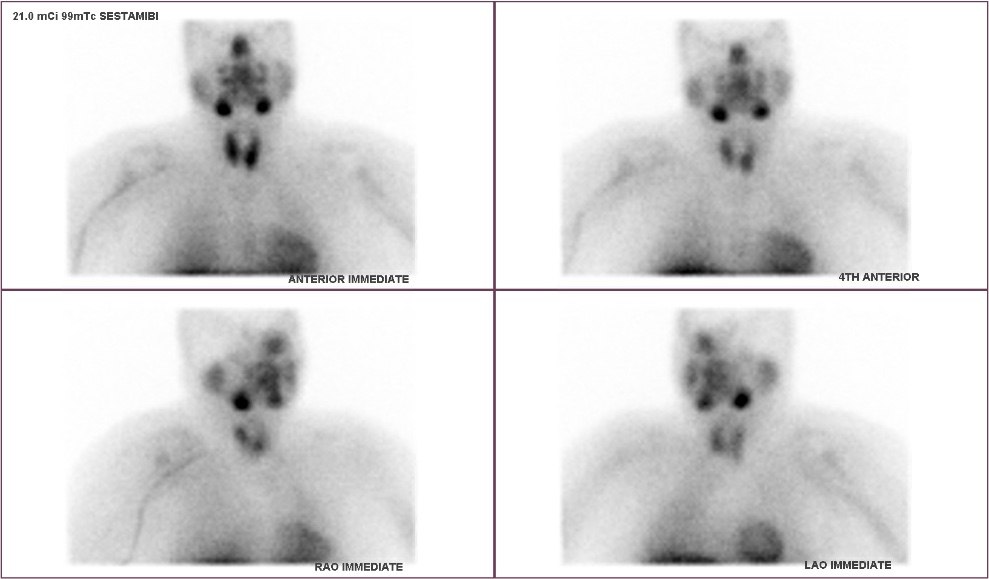

After diagnosis, the next question is whether to pursue treatment. Any patient younger than 50 with hyperparathyroidism should be recommended for surgery. This patient found us and we met in clinic. We reviewed her blood work and discussed the surgery and recovery. On the day of surgery, her nuclear medicine scan was relatively unimpressive. Her ultrasound also did not see a tumor.

You can see the large left upper parathyroid adenoma that was removed that managed not to show up on the scan. In the hands of the wrong provider, a patient with these images might never make it to the operating room. Make sure you have your case evaluated by experts!

Sestamibi scanning is the preferred way to localize diseased parathyroid glands prior to an operation. HOWEVER, sestamibi scans are wrong at least 50% of the time.